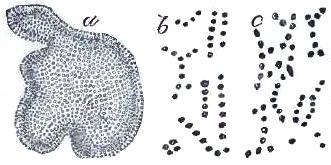

| FIGURE | |

| 1. | MICROCOCCI |

| 2. | BACTERIA |

| 3. | BACILLUS MALARIÆ |

| 4. | BACTERIA FROM GELATIN SOLUTION |

| 5. | VIBRIOS IN GELATIN CULTURE-FLUID |

| 6. | PROTOCOCCUS FROM SLIDES EXPOSED OVER SWAMP-MUD |

| 7. | BACILLI FROM SWAMP-MUD |

| 8. | BACILLI FROM SEPTICÆMIC RABBIT |

| 9. | BACILLI FROM HUMAN SALIVA |

| 10. | BACILLUS ANTHRACIS |

| 11. | BACILLUS TUBERCULOSIS |